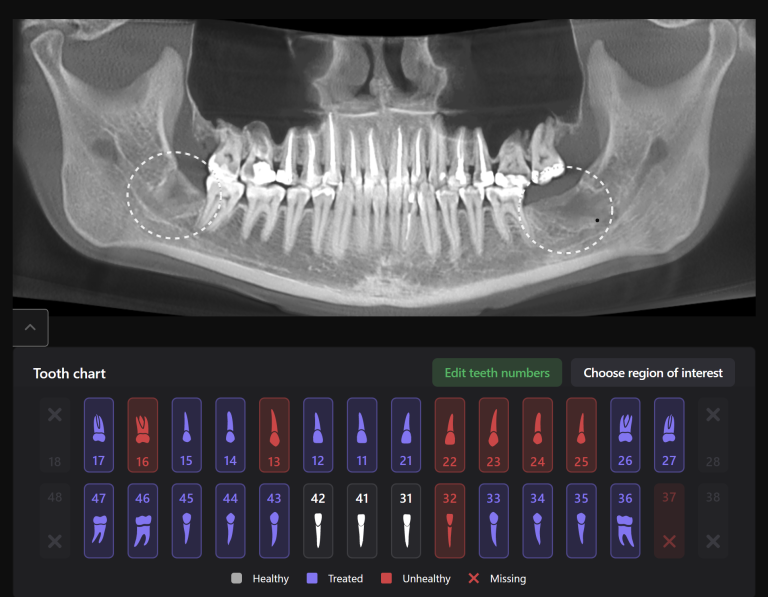

Solution: The automated process of segmentation and formation of 3D models from DICOM files allows extracting individual structures for subsequent 3D printing. The printed model of the third molar, taken from the “STL” module of Diagnocat, is used to prepare the socket for the transplanted tooth. The 3D reconstruction generated using Diagnocat displays the structure of the jaws and teeth and enables the visualization of tooth 37 (Universal 18) with periapical lesion around the roots. In this case, Diagnocat serves as a communication tool that helps convince the patient of the importance of timely implementation of the proposed treatment plan.